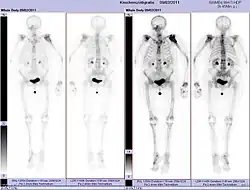

Pathologische Fraktur des Oberarmknochens bei einer Metastase eines Nierenzellkarzinoms -

Pathologische Fraktur des linken Oberarms bei Knochenmetastase einer Patientin mit Brustkrebs -

Ganzkörperknochenszintigramm mit 99mTc-HDP der Patientin mit der Oberarmfraktur aufgrund einer Brustkrebsmetastase